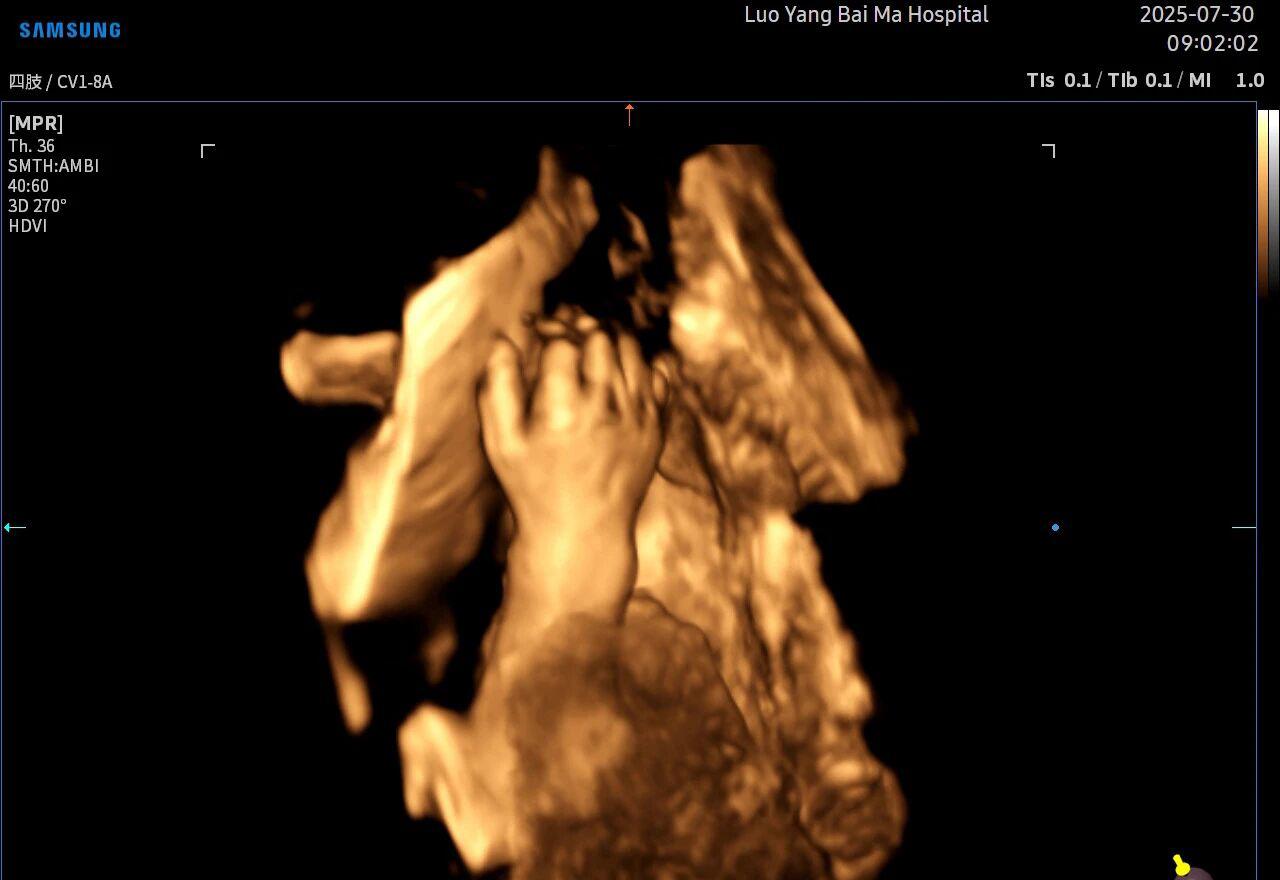

孕中期(通常在22-28周)的大排畸检查是整个孕期至关重要的环节之一。其目的在于系统地筛查胎儿是否存在结构性异常,如唇裂、脊柱裂、大脑、心脏、骨骼发育不良等问题。在这一关键检查中,5D智能彩超凭借其技术特性,展现出了显著的优势。

5D智能彩超拥有更高的分辨率和更强的图像处理能力,能够呈现出接近“IMAX电影画质”的细腻影像 。它采用一种被称为“水晶成像”的技术,能够穿透组织,将胎儿的骨骼、器官和组织结构以极其清晰、立体的形态展示出来。这种高清晰度对于观察胎儿微小的解剖结构细节至关重要,例如手指、脚趾、耳廓形态等,有助于医生发现一些在传统超声下不易察觉的细微异常,为排畸诊断提供了更丰富的视觉信息。

传统超声检查有时会因为胎儿体位、羊水量等因素的限制,导致某些部位观察不清。5D智能彩超技术能够实现对目标结构进行360°全方位、多切面的自由旋转观察。医生可以像“雕塑家”一样,从任意角度审视胎儿的解剖结构,尤其对于形态复杂的心脏、颅脑和脊柱等部位,这种能力可以极大弥补单一平面的局限性,帮助医生更全面地评估其发育状况。